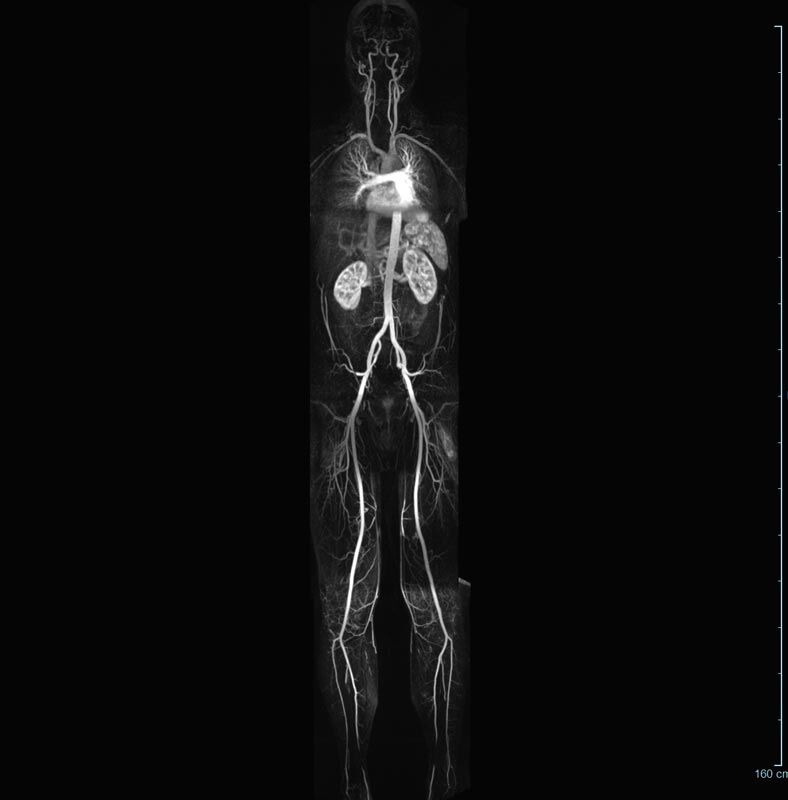

Aorta

• Bauchgefäße

• Erfassung und Verlaufskontrolle bei arteriellen Aneurysmen (Aussackungen der Arterien), vor allem der Bauchaorta

• Darstellung von Gefäßengen an Nierenarterien, Baucharterien und Becken-/Beinarterien

MR-Angiografie (MRA)

Ganzkörper Angiographie mit Kontrastmittel

• MR-Angiographie mit Kontrastmittel

• Erfassung arterieller und venöser Gefäße/Bypässe aller Körperregionen mit 3D-Rekonstruktion

• je nach klinischer Fragestellung zeitaufgelöste MR-Angiographie (4D-MRA) z.B. bei Frage arteriovenöse Fistel/ Shunt oder Darstellung Unterschenkelarterien vor geplanter Bypassoperation.